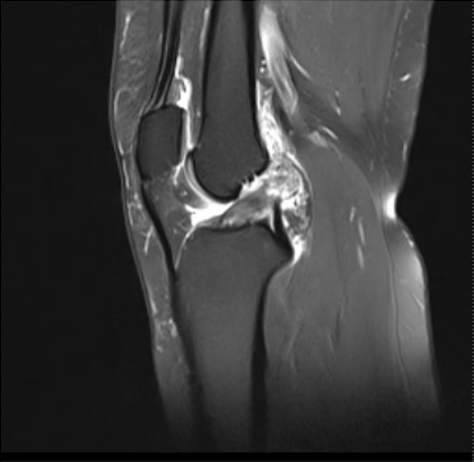

检查显示,患者的前交叉韧带断裂。